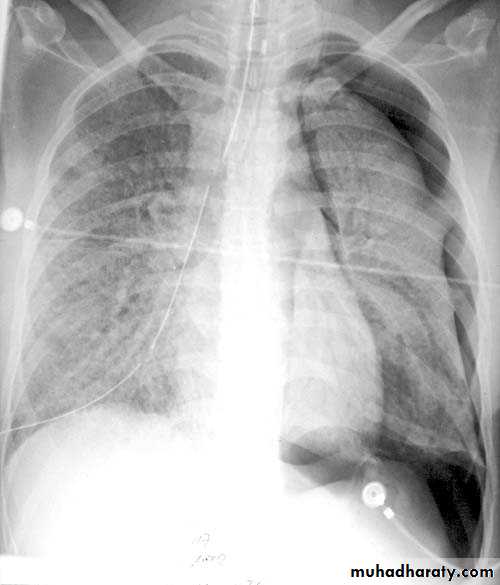

Pleural effusion ( free)

Massive pleural effusion